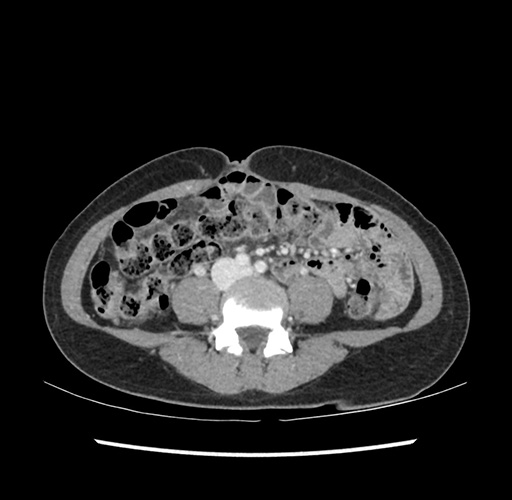

Imaging Analysis

Look through the patient's CT scan to identify any areas of concern for the necessary procedure.

Based on your CT findings, which issue(s) would give reason for "planned slowing down moment(s)" in this case?